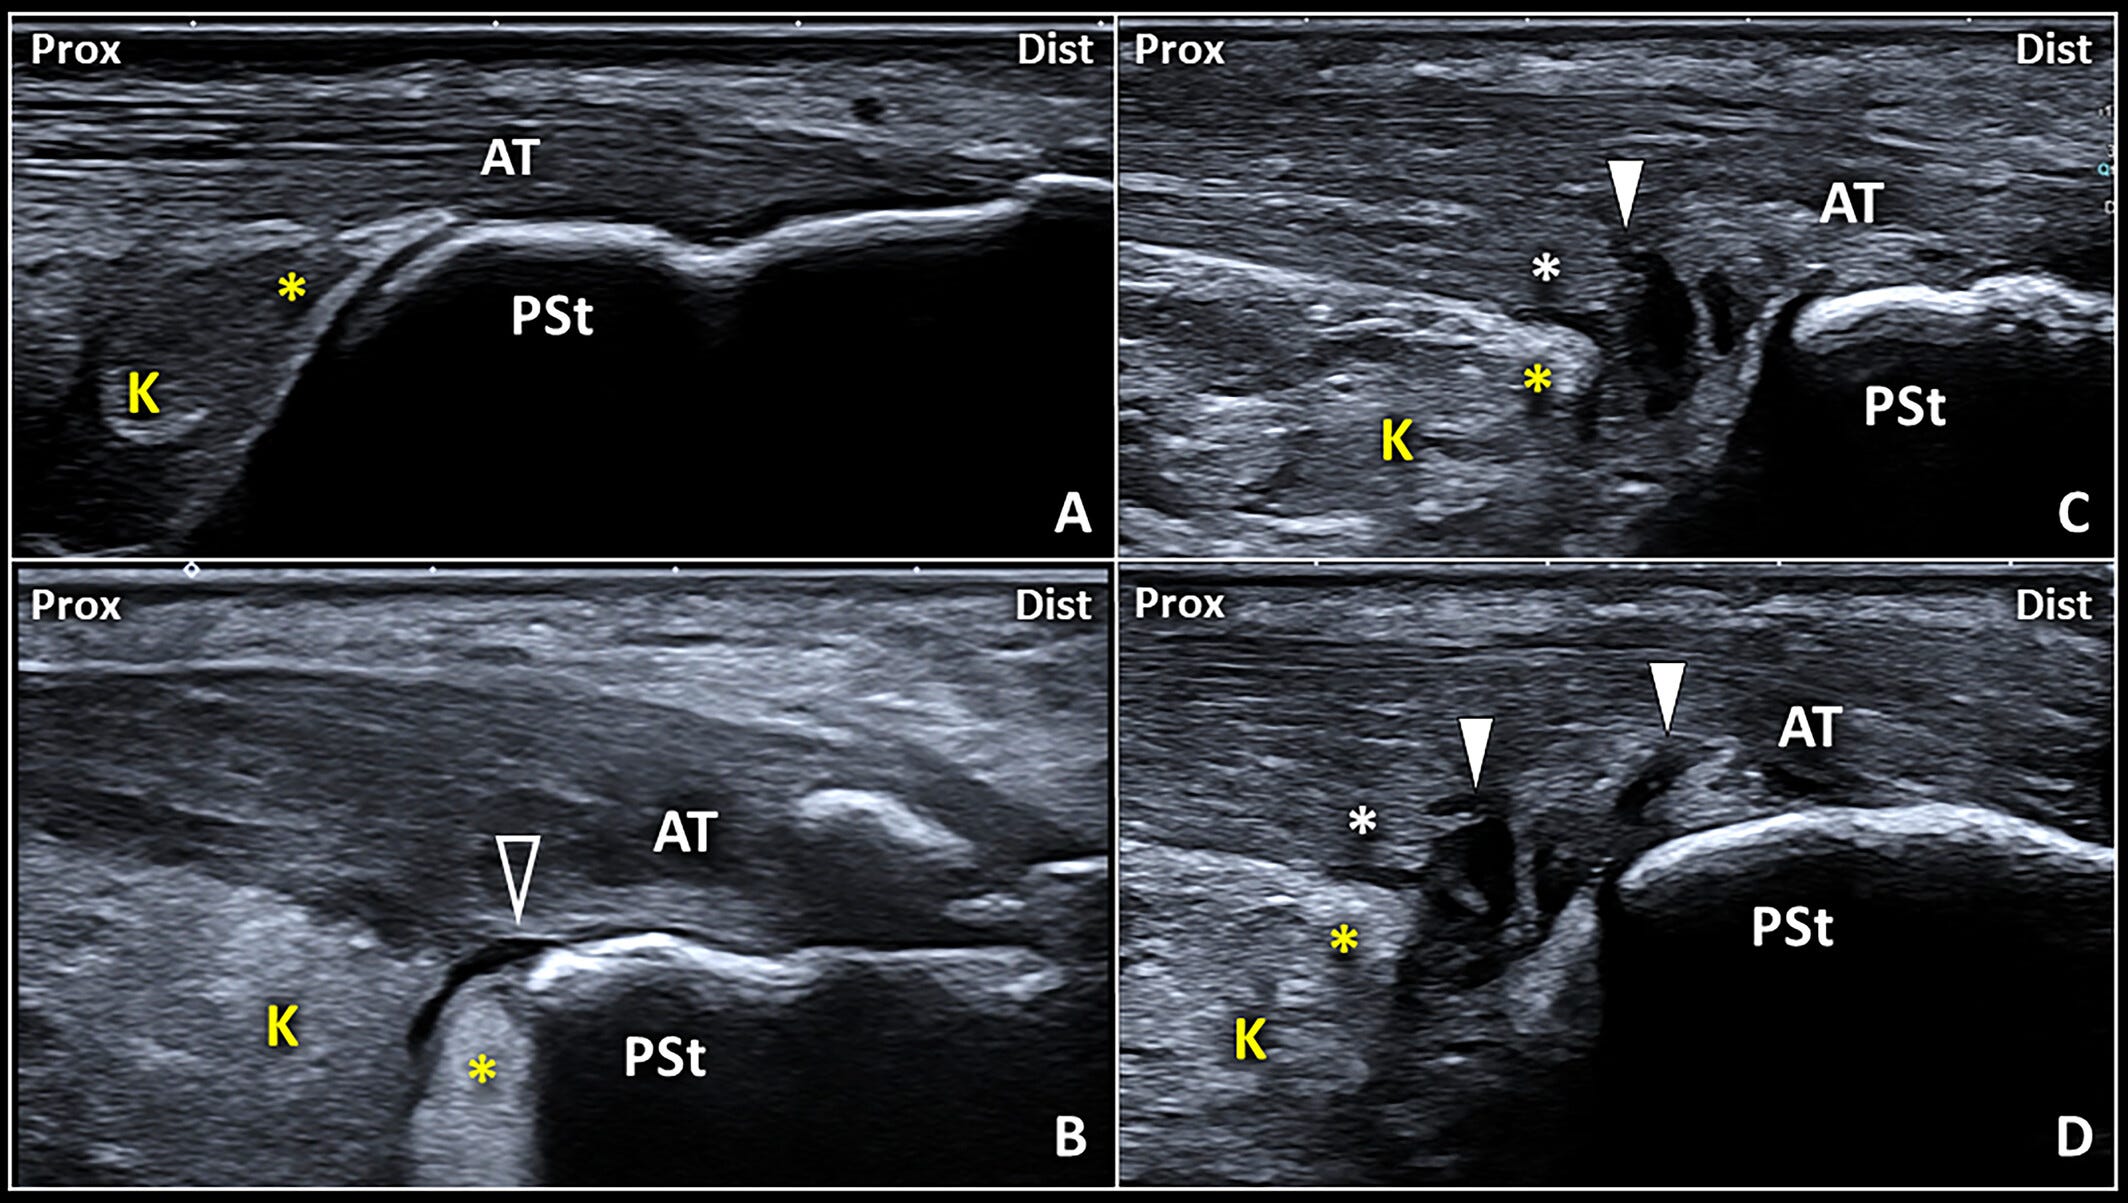

Patrones ecográficos de la interfaz bursa retrocalcánea–tendón de Aquiles.

En condiciones normales (A), la cuña posteroinferior (PIW) de la almohadilla grasa de Kager (K) (asterisco amarillo) contacta con la superficie profunda del tendón de Aquiles (AT).

Por el contrario, un derrame anecoico localizado en el receso posterior de la bursa retrocalcánea (RCB) (B) puede desplazar la cuña grasa (asterisco amarillo) y mostrar una interfaz lineal bursa–tendón (puntas de flecha vacías).

En pacientes con disrupción de las fibras profundas del tendón (asterisco blanco), la interfaz bursa–tendón irregular y mal definida (C y D) presenta digitaciones sinoviales de la RCB (puntas de flecha blancas) que penetran en el tendón de Aquiles.

Dist: distal; Prox: proximal;

PSt: tuberosidad posterosuperior del calcáneo.

Este patrón no solo indica una comunicación anómala entre la bursa y el tendón, sino que puede considerarse como un signo indirecto de daño en el fibrocartílago sesamoideo del tendón. Es decir, la frontera natural entre ambas estructuras ha sido sobrepasada. Algo así como cuando en Inception los sueños empiezan a colapsarse y lo que debía estar separado comienza a mezclarse, dejando de ser fiable lo que antes parecía estable.

Desde el punto de vista clínico, esta situación exige especial atención. Si se va a realizar una infiltración ecoguiada en la bursa, es fundamental distinguir bien si hay o no una conexión patológica con el tendón. De lo contrario, existe el riesgo de que el corticoide inyectado migre hacia el interior del tendón, con posibles consecuencias negativas, como debilidad estructural o rotura.

Por ello, en presencia de derrame y una interfaz borrosa, es clave realizar una evaluación dinámica: ya sea con flexo-extensión del tobillo o presionando manualmente el espacio retrocalcáneo. Estos movimientos pueden provocar la migración del líquido hacia el interior del tendón, revelando lesiones que podrían pasar desapercibidas en una imagen estática.